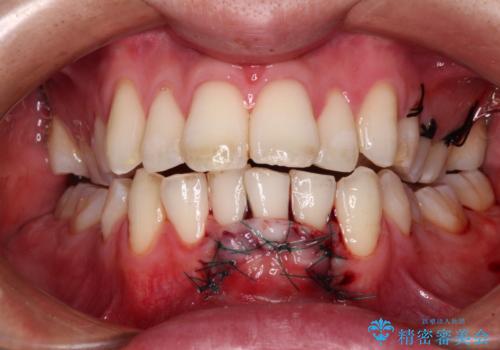

歯肉が非常に薄く、必要な被覆量が多いことから、1度の処置では十分な被覆は難しく、2度処置を行うことになる可能性が高いとお伝えしました。

1回目の処置で多少は被覆され歯肉が厚くなりましたが、十分とは言えなかったため、2回目の処置を行いました。